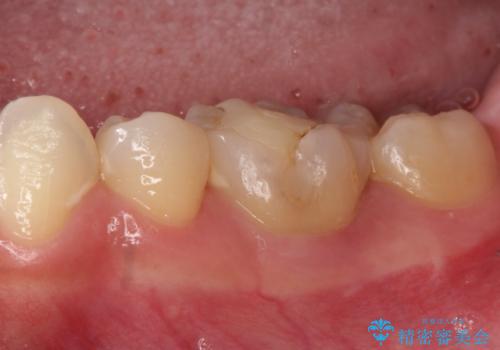

【セラミッククラウン】適合の悪いアンレーのやり替え

- 過去に他院で治療された奥歯が気になりご来院されました。

セラミッククラウンによる治療を希望されていたため根管治療から処置を行っています。